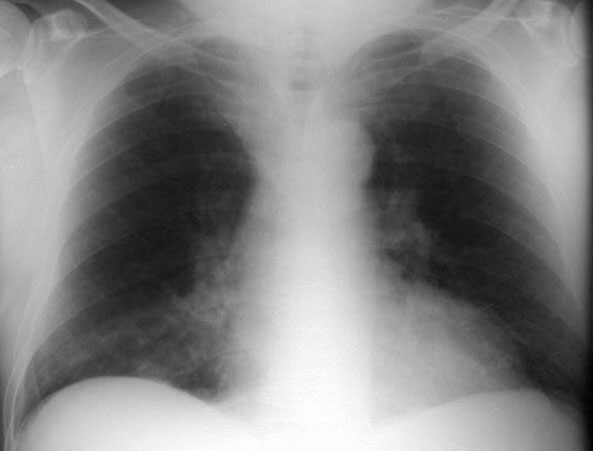

SIGNO DEL TRIÁNGULO SUPERIOR

Signo de colapso del lóbulo medio derecho o del lóbulo inferior derecho que consiste en la presencia de una densidad triangular en la zona paramediastínica derecha (flecha roja) que corresponde a la zona de convergencia de las líneas pleuromediastínicas anteriores, desplazadas a la derecha por el colapso. El descenso de la posición de la cisura menor (flecha blanca) confirma la pérdida de volumen en el lóbulo medio, en este caso.

Otro ejemplo de este signo, en este caso por pérdida de volumen en el lóbulo inferior derecho. No es visible la cisura menor, pero puede observarse el descenso del hilio derecho.